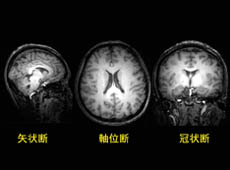

これまでに得られたいくつかの画像を紹介したい。図1は3次元形態画像から脳の3方向の断面を抽出した結果である。神経細胞が集積する灰白質(画像でも灰色に見える),神経細胞同士の連絡をする神経線維の束である白質(画像でも白っぽい)が明瞭に識別できる。この違いを用いて,両者を定量する方法も検討中である。また,図2では脳のほぼ中央両側に存在する側脳室と呼ばれる部位を抽出した(画像ではX字状の暗い部分)。上段が男性,下段が女性で左から右に年齢順に並べた。まだ,わずかな測定例ではあるが,年齢とともに脳室が拡大していく様子が明瞭に認められる。高精細の形態画像では,このほか男性と女性で性差があるといわれる脳梁の形態や厚さ,脳内のホルモン分泌器官である脳下垂体の形状にも注目している。図3は主に視覚に関与することが知られている脳の後ろの部分(後頭葉)に存在する代謝物を測定したスペクトルを示す。上段は陽子(1H)のスペクトルで,神経細胞のマーカーであるN-アセチルアスパラギン酸や,代表的な興奮性神経伝達物質であるグルタミン酸等の代謝物が認められる。下段はリン(31P)のスペクトルで,脳内のエネルギー代謝を司る高エネルギーのクレアチンリン酸やATPが明瞭に観測できる。これらのスペクトルは10分間の測定で得られ,世界で初めて両スペクトルを同時に得られるようになった。これらのスペクトルから脳の生理学的状態を表す情報が得られると期待している。

図1.脳の3次元形態画像から切り出した,3方向の断面

横顔の断面を矢状断,体軸に直交する断面を軸位断,顔面に並行な断面を冠状断と呼ぶ。